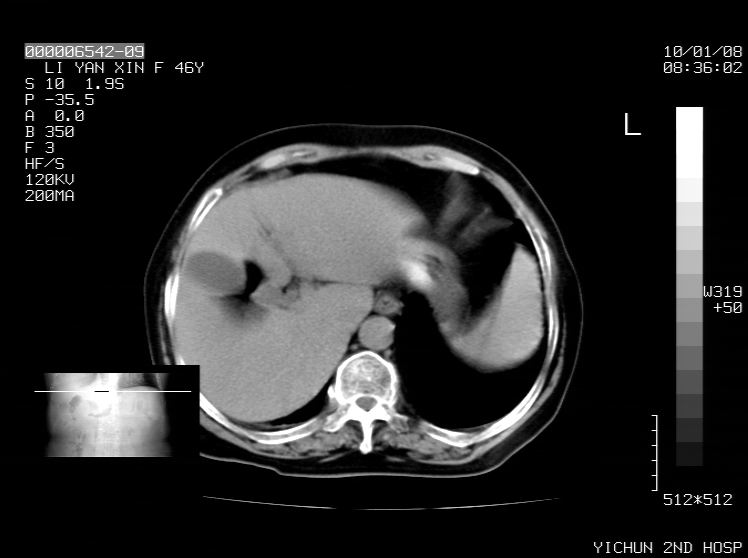

右侧膈膨升,胆囊壁厚,右侧肾脏缺如。病史?

右侧膈膨升,肝内钙化灶,胆囊壁厚,右侧肾脏缺如。病史?

右膈膨出,肝脏变异,肝内钙化,右肾缺如,脾大。

右侧膈膨升,肝内胆管结石?

右侧膈膨升,胆囊壁厚,右侧肾脏缺如,增强,腔静脉旁是否是移位肾

肝脏变异致膈升高,肝左叶肝内胆管结石.右肾萎缩,左肾代偿肥大.

胆囊ct未见确切异常,请结合b超。右侧肾窝未见确切肾脏影,右肾萎缩?异位?

右侧膈膨升,肝内钙化灶,胆囊壁厚,右肾萎缩或发育不良。